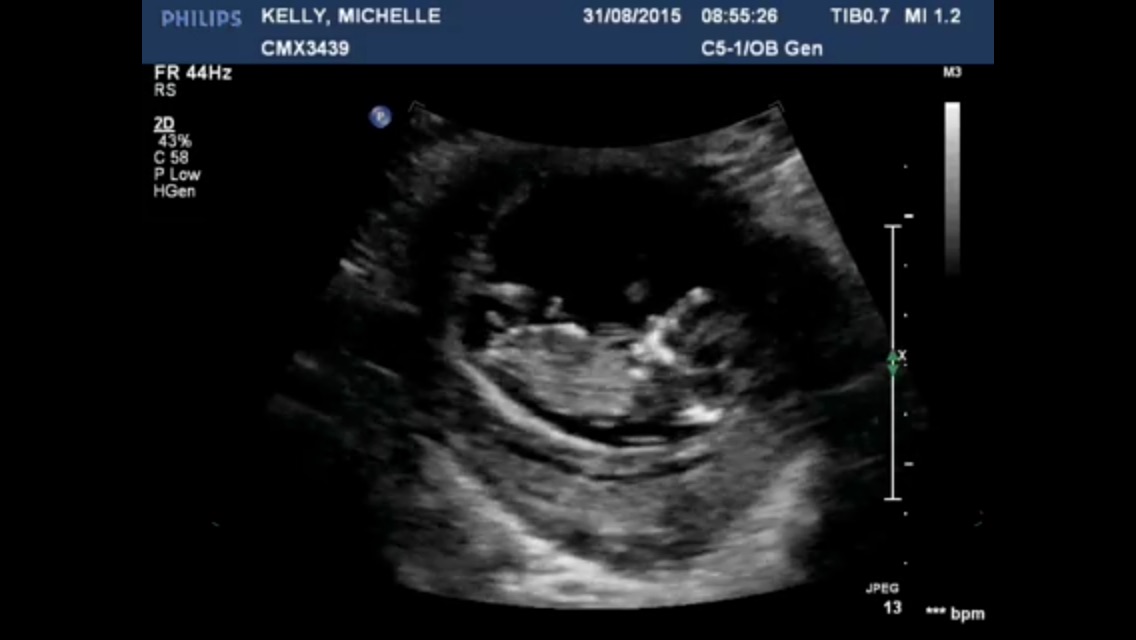

My first time visiting here id love you guys to take a guess if possible? I'm not even sure if the nub is visible, there is so much going on!

If that is the nub, then definitely boy!

I think boy

I think that's cord in the second. I'm not sure about the first either. Could be cord again as it's is super pointy and big for only 12 weeks 1 day.